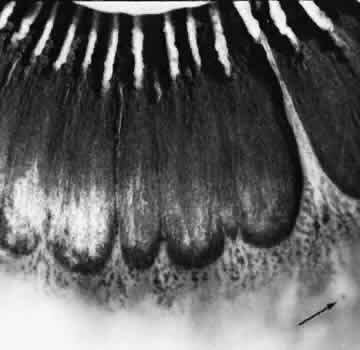

CYSTIC RETINAL TUFT

Larger than a noncystic tuft, the cystic retinal tuft is a nodular projection of retinal tissue that extends from a vitreous attachment at the apex to a base that is more than 0.1 mm in diameter and surrounded by cystic retinal degeneration (Fig. 38). Single ormultiple cystic retinal tufts may be located within or posterior to the vitreous base. On microscopic appraisal, the tuft, attached internally to a vitreous strand, is composed of degenerated and proliferated retinal cells that may contain a few pigment granules (Fig. 39). There may also be degeneration of the adjacent retinal pigment epithelium.

Fig. 38. Cystic retinal tuft in peripheral retina of a 14-year-old boy. Tuft measures 0.47 mm at its circular base, is 3.7 mm from the ora serrata, and contains many microcysts with dense walls. (× 19.)

Fig. 39. Microscopic features of the lesion seen in Figure 38. Surface of the tuft is irregular, with layer of dense-staining glial cells that partially surround subsurface microcysts. Degeneration of neurons, formation of microcysts, and pigment dispersion occur in deeper layers. Outer retina beneath lesion shows marked degeneration of photoreceptor cells. Patterns of vitreous over lesion are distorted, and coarse bundles of vitreous fibrils blend with irregular surface of tufts. (Periodic acid-Schiff; × 180.)

Cystic retinal tufts are present at birth; they are evident in 5% of adults, are bilateral in 6% of affected patients, and thus are detected in 2.5% of adult eyes (see Table 3). Although cystic retinal tufts show no quadrant predilection, 78% occur in the equatorial (extrabasal) zone, and 80% occur singly in eyes of affected patients.

On clinical examination, cystic retinal tufts are readily visualized and are distinguishable from noncystic tufts by size and other characteristics. Cystic retinal tufts are of importance because they may be avulsed by vitreous traction, with or without posterior vitreous detachment leading to retinal tear or retinal detachment.